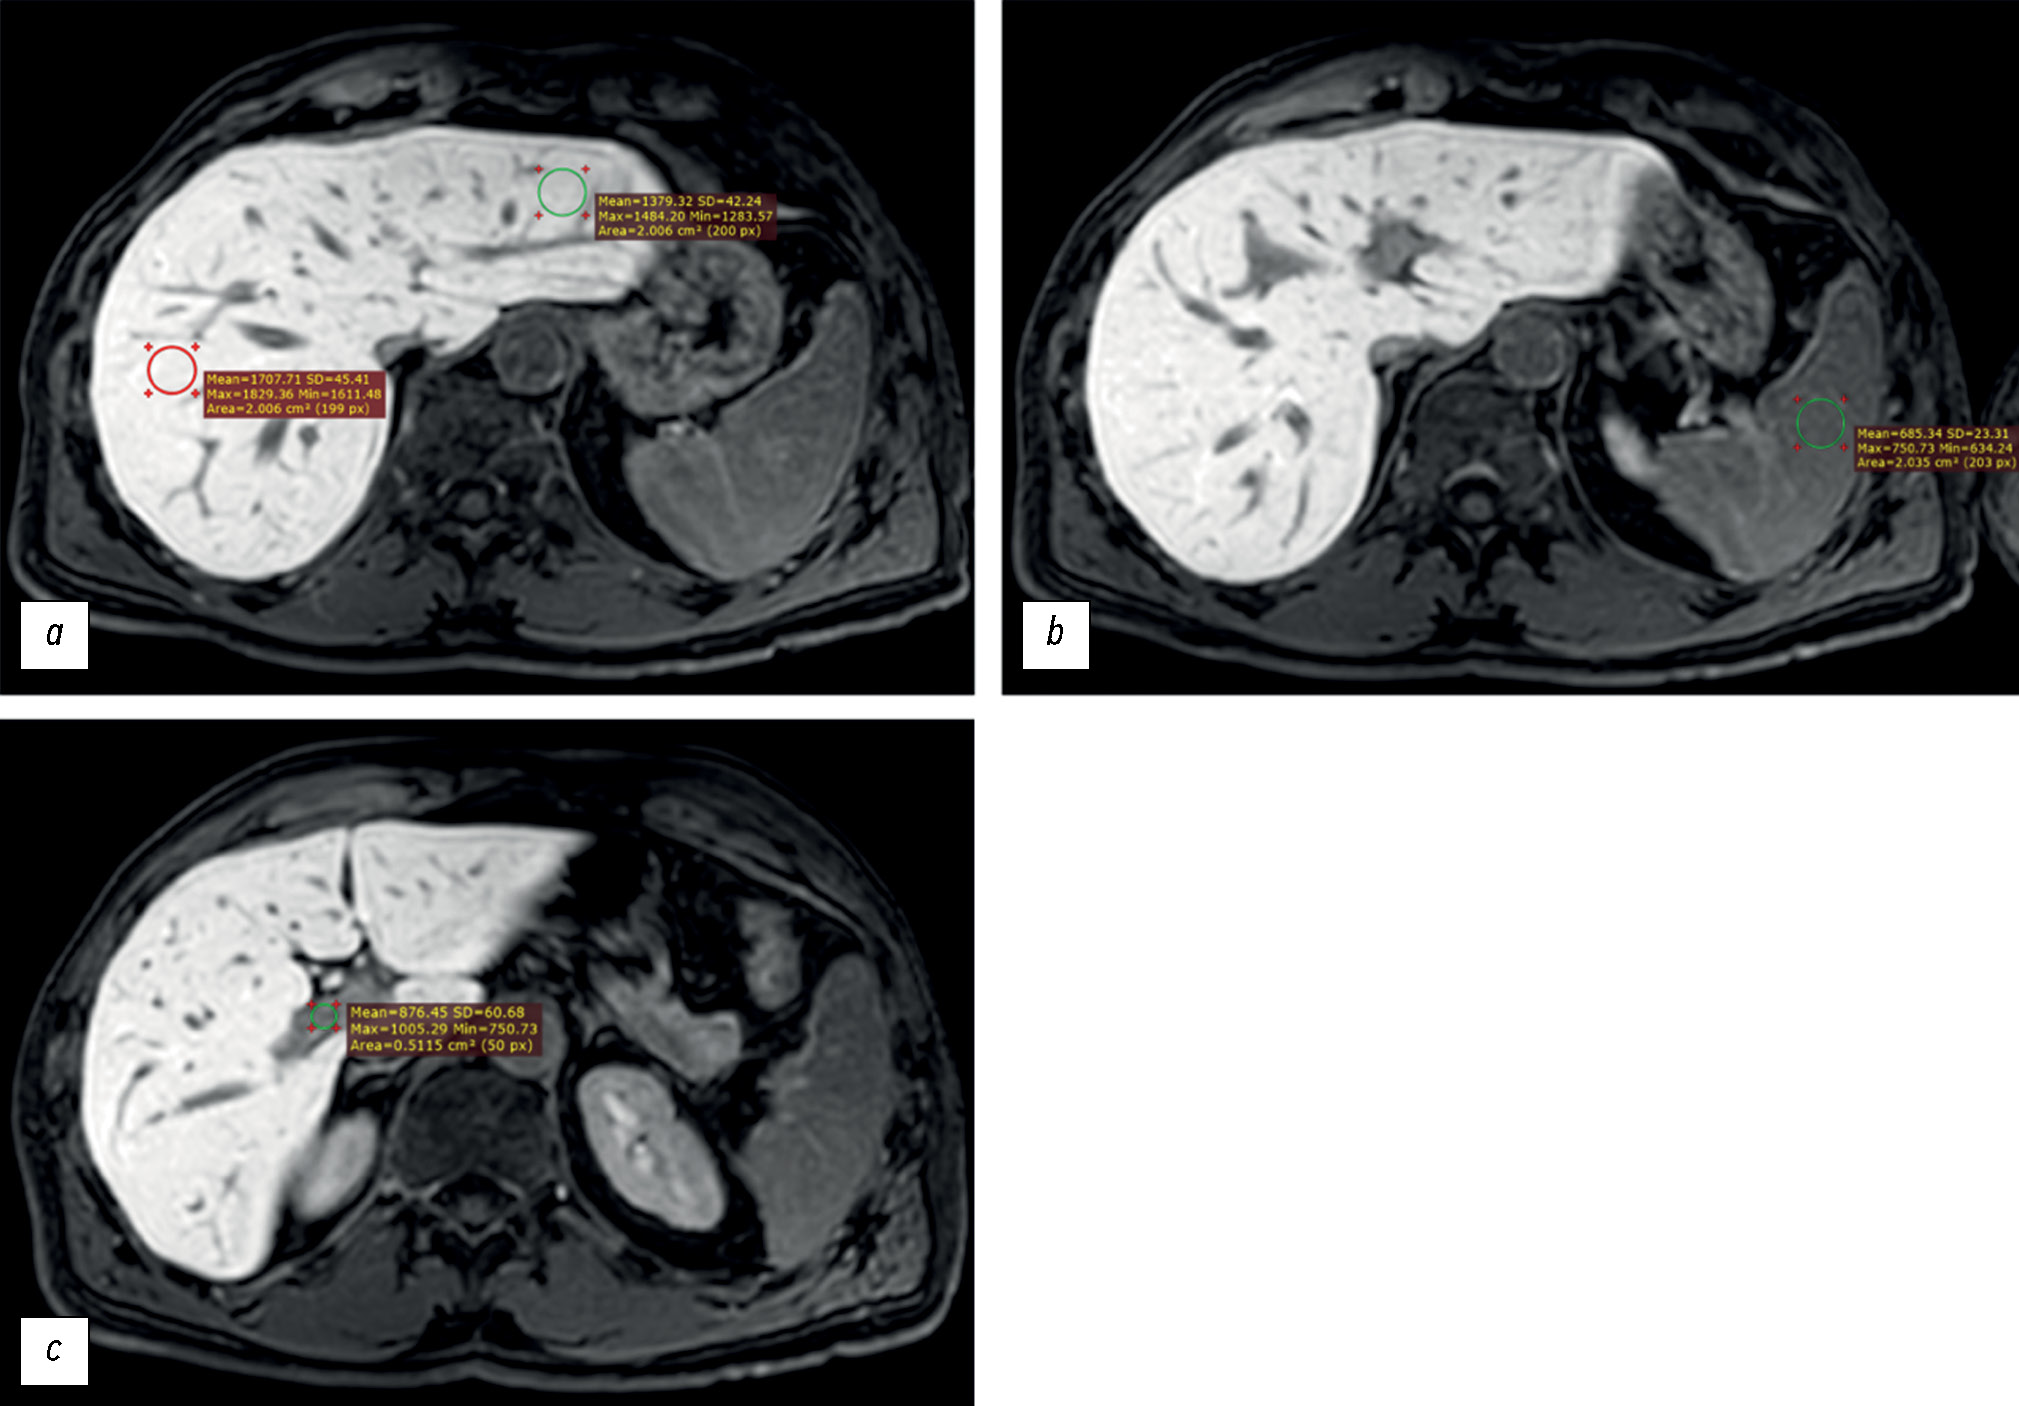

Liver function assessment based on hepatobiliary contrast agent-enhanced magnetic resonance imaging

BACKGROUND: Liver function assessment is very important in clinical practice. The use of magnetic resonance imaging for the anatomical and functional evaluation of the liver is possible in actual clinical practice.

AIM: To examine the possibility of using hepatobiliary contrast-enhanced magnetic resonance imaging for the evaluation of liver function.

MATERIALS AND METHODS: Datasets of patients who underwent gadoxetic acid-enhanced magnetic resonance imaging were retrospectively reviewed. Patients were divided into two groups: group 1 included patients with impaired liver function, and group 2 included those with normal liver function. Based on magnetic resonance imaging in the hepatobiliary phase, the liver parenchyma signal intensity and its ratio to spleen signal intensity and portal vein signal intensity were estimated. Differences among these parameters were compared between groups. The correlation between liver parenchyma signal intensity and laboratory blood tests reflecting liver function (total bilirubin, albumen, aspartate aminotransferase, alanine aminotransferase, alkaline phosphatase, gamma glutamyl transpeptidase, and prothrombin time) were analyzed.

RESULTS: Datasets of 53 patients (25 men and 28 women, aged 24–84 years) were analyzed. Group 1 included 19 patients, whereas group 2 included 34. The median liver parenchyma signal intensity was 919.05 [669.65; 1258.35] in group 1 and 1525.13 [1460.5; 1631.4] in group 2 (p=0.0000001). The median ratio of liver parenchyma signal intensity to spleen signal intensity was 1.2 [1.04;1.7] in group 1 and 1.7 [1.46; 1.96] in group 2 (p=0.00076). The median ratio of liver parenchyma signal intensity to portal vein signal intensity was 1.44 [1.29; 1.83] in group 1 and 1.6 [1.43; 1.83] in group 2 (p=0.1). The estimated correlation values between liver parenchyma signal intensity and blood tests parameters were as follows: total bilirubin (r=–0.61; p=0.000001), albumen (r=0.13; p=0.61), aspartate aminotransferase (r=–0.57; p=0.000009), alanine aminotransferase (r=–0.44; p=0.001), alkaline phosphatase (r=–0.45; p=0.0007), gamma glutamyl transpeptidase (r=–0.5; p=0.0003), prothrombin time (r=–0.34; p=0.04).

CONCLUSION: The study reflects the ability to assess liver function using indices (liver parenchyma signal intensity and its ratio to spleen signal intensity) derived from gadoxetic acid-enhanced magnetic resonance imaging. However, this study did not confirm the assumed effectiveness of using the liver parenchyma signal intensity to portal vein signal intensity ratio as an index of liver function. A significant inverse correlation was identified between liver parenchyma signal intensity and blood test parameters in reflecting liver function, except for albumin. The results indicate the possibility of using magnetic resonance imaging to assess liver function.